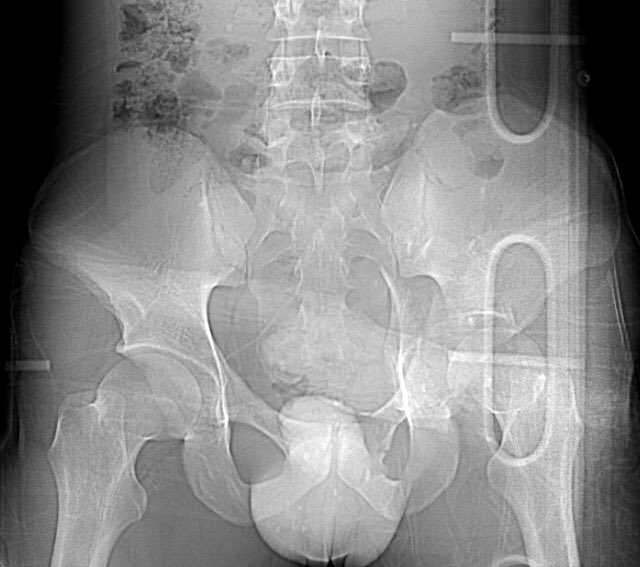

Isolated injury in a 38yo male driver after an automobile crash - can you identify the radiographic lines and fracture pattern?

The postop CT helps us assess and understand the articular reduction and implant applications best